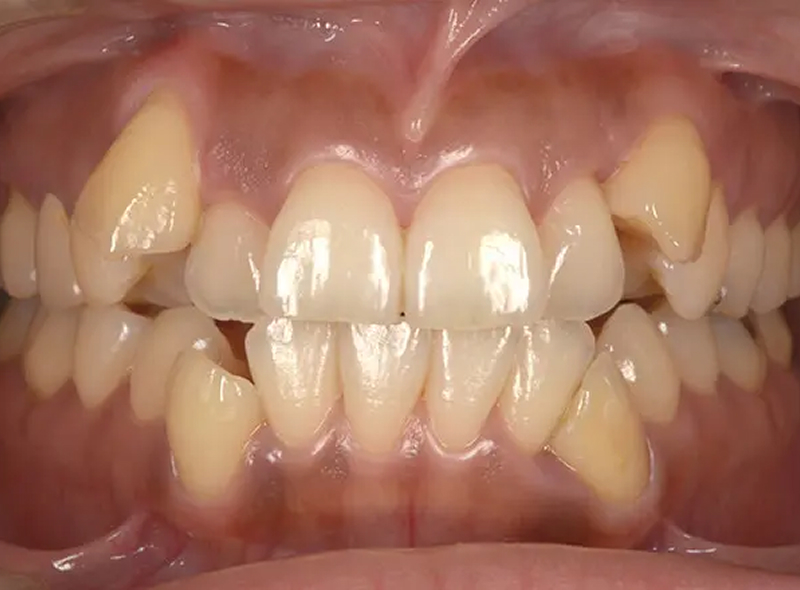

Case01全体的な凸凹を改善した症例

大学4年生の5月に来院して、卒業までに矯正治療が終わるかということでした。就職すると歯科医院に通院するのが難しいからと強い希望を持っていました。診査の結果、歯列の拡大で行えギリギリ間に合う診断をしました。矯正治療後、審美治療を行う時間もあり、十分、納得のいく治療をすることができました。

口元比較

Before

After

初診 2017.5.24

矯正治療開始 2017.6.19

矯正治療終了(9か月) 2018.3.6

ファイナル 2018.3.16

| 主訴 | 全体的な凸凹を治したい |

|---|---|

| 診断 | 両側アングル1級の叢生 |

| 矯正方法 | オーバーレイアーチを用いたマルチブラケット |

| 矯正期間 | 9か月・10回 |

| 費用 | 750,000円(税別) |

| 調整料 | 月1回 5,000円(税別) |